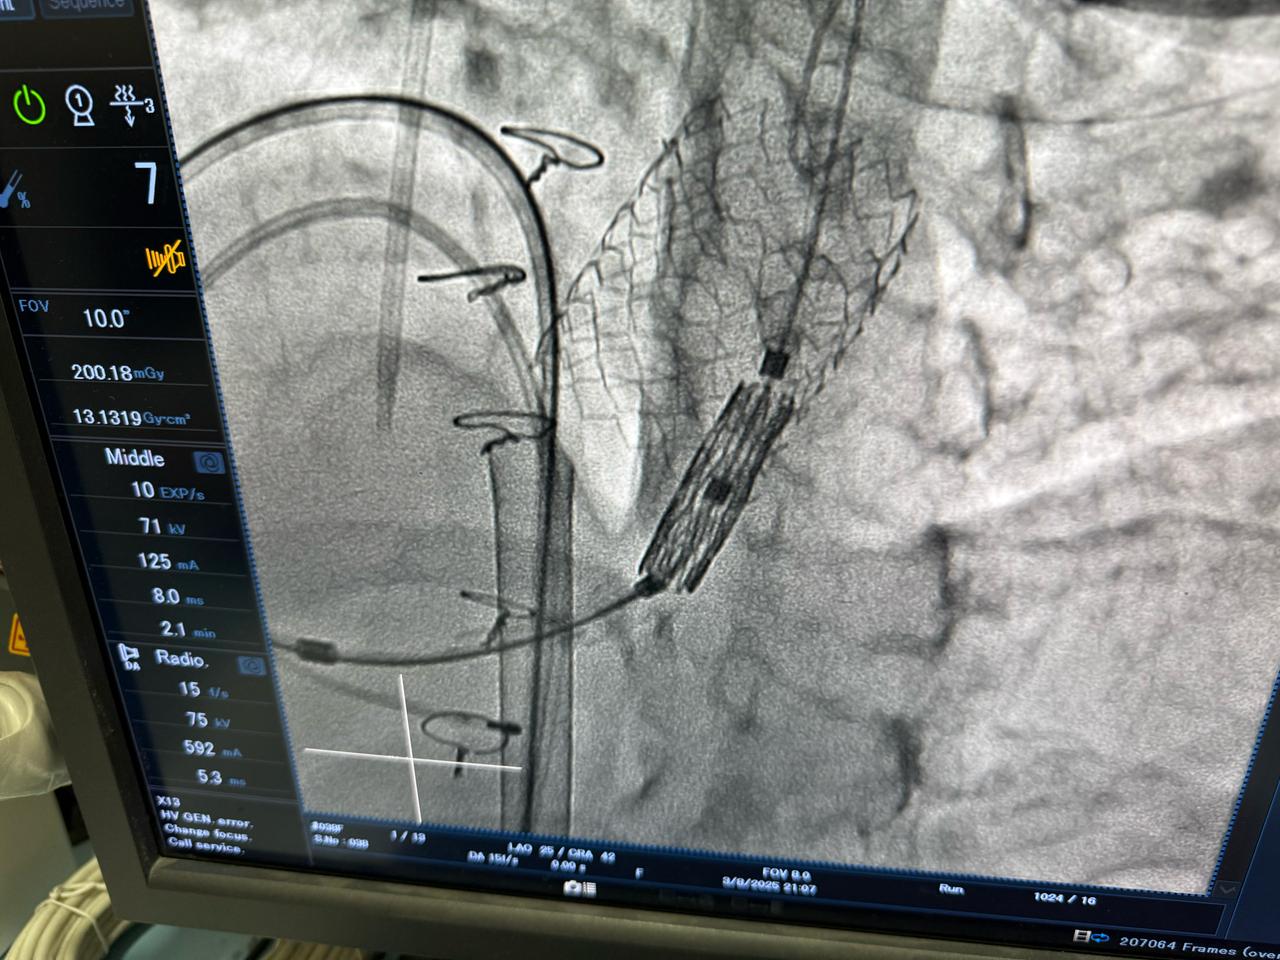

أعلنت وزارة الصحة والسكان، عن نجاح عملية دقيقة لتغيير الصمام الرئوي بالقسطرة لشابة تبلغ من العمر 23 عامًا، كانت تعاني من ارتجاع شديد بالصمام الرئوي نتيجة جراحة رباعي فالوت السابقة، وهو أحد أكثر العيوب الخلقية القلبية تعقيدًا.

وصرّح الدكتور حسام عبد الغفار، المتحدث الرسمي لوزارة الصحة والسكان، بأن العملية أُجريت باستخدام أحدث التقنيات العالمية داخل أكاديمية قلب المبرة، التابعة للمؤسسة العلاجية، على يد نخبة من الخبراء المصريين، مؤكدًا أن هذا الإجراء الطبي المتقدم، الذي تجاوزت تكلفته مليون جنيه، يعكس قدرة الفرق الطبية المصرية على تنفيذ أدق التدخلات القلبية وفق أعلى المعايير الدولية.

وجرت العملية تحت إشراف الدكتور محمد إبراهيم شقوير، رئيس المؤسسة العلاجية، والدكتور هشام الفخراني، مدير مستشفى مبرة مصر القديمة، وبقيادة فريق طبي متخصص برئاسة الدكتور محمد صبري، رئيس قسم القلب، والدكتور أحمد السواح، مدير وحدة القسطرة، والدكتور علي جلال، مدير وحدة الأمراض الخلقية.